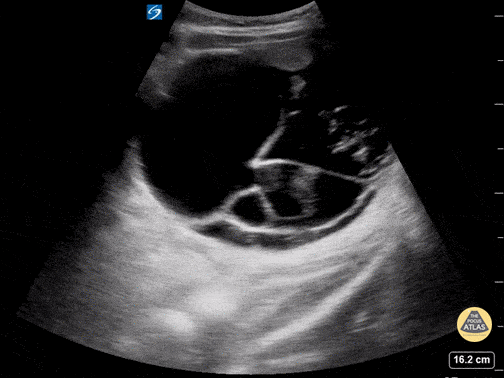

This is a transverse view of the RLQ in a young female who presented with dysuria and a history of constipation. On physical exam, a visible mass was noted to the right of her umbilicus. Urinalysis and urine pregnancy test were negative. Bedside transabdominal ultrasound revealed a septated mass containing heterogeneous material with scattered hyperechoic foci most consistent with an ovarian teratoma. Allison Perkins MD, PGY-1, Jared Toupin MD, PGY-2 Carnegie Mellon University Emergency Medicine Residency